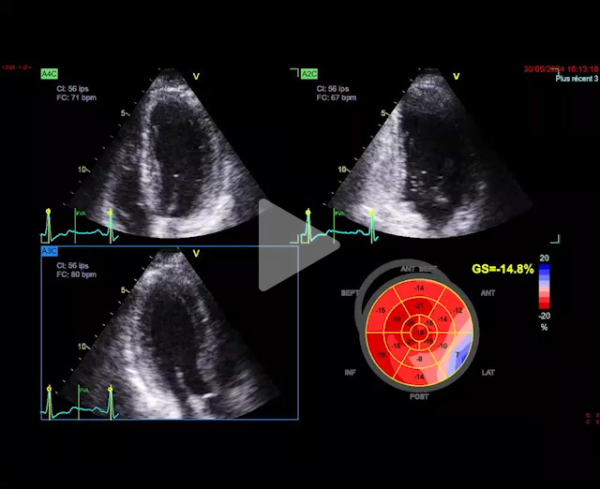

L'ETT montre :

- Dilatation modérée du VG. FEVG à 30%

- Cardiopathie hypertrophique sévère excentrique

- Flux mitral restrictif

- Ventricule droit non dilaté

- Paroi libre épaissie

- Minime épanchement péricardique circonférentiel

Réévaluation ETT à 6 mois de l’épisode d’HTA sévère :

- FEVG 44%, GLS -11%

- HVG sévère stable, VG non dilaté